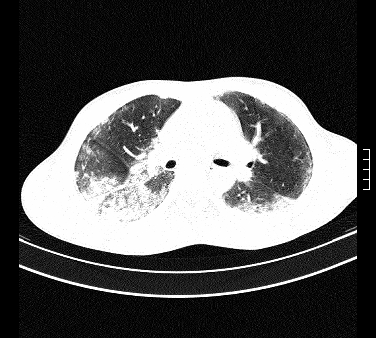

患者,男,17岁,系我院急诊科收治的一例百草枯中毒患者,做ct检查时,距离服药的时间为3天。上传与大家分享

补充:百草枯进入人体内主要分部于肺和骨骼,肺部损伤24小时内出现水肿,2-3天内出现急性呼吸窘迫综合征,1-2周内出现肺纤维化。(引自陈灏珠,实用内科学12版)